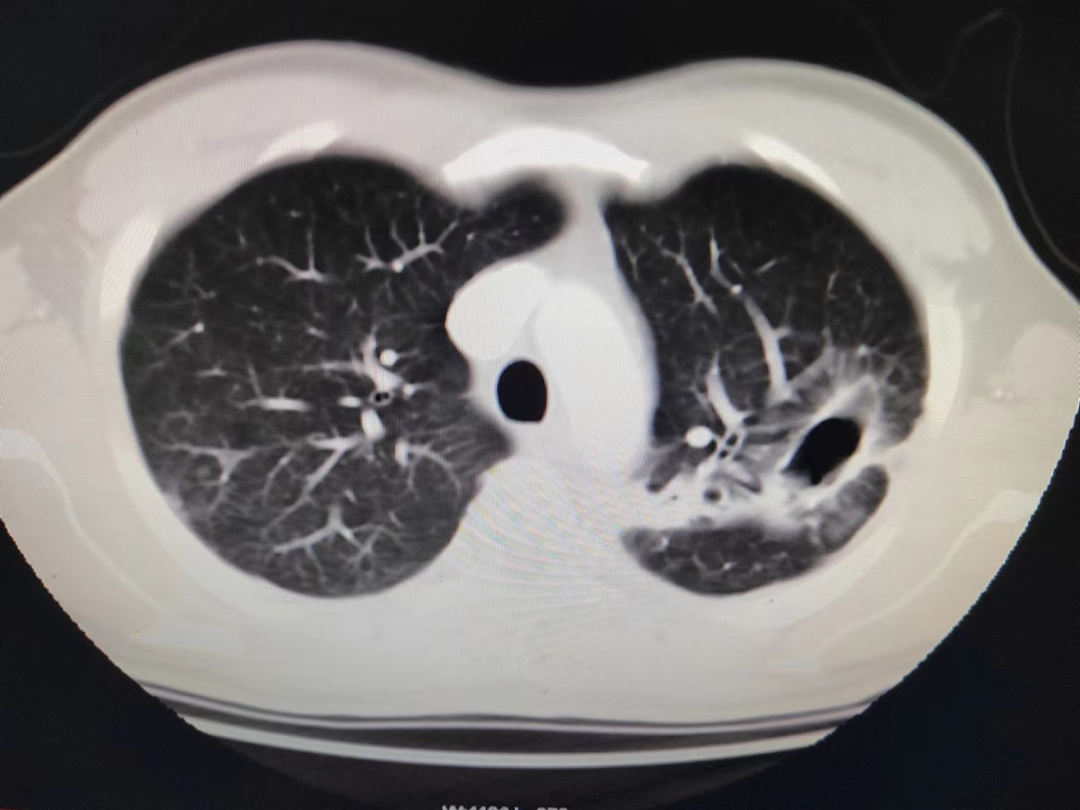

术前左肺空洞型病灶

术前胸部CT,见空洞内曲菌球